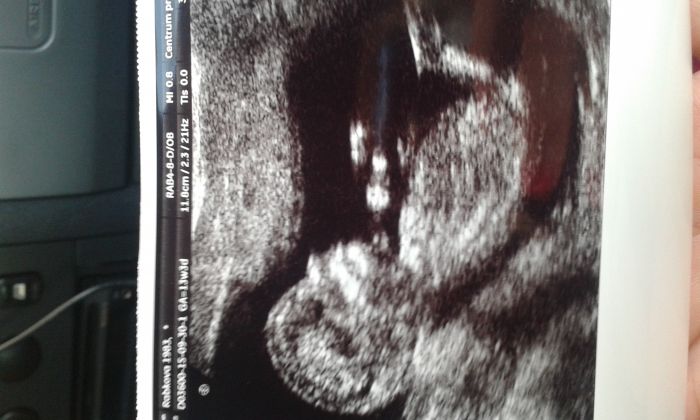

[794697] Stanko,krasna fotecka! Nebuj,vsechno bude dobre.Mimco je bojovnik,jinak uz by tady prece nebylo.

[794697] ma to par centimetru a uz to vypada jako clove :O to je neuveritelny...krasna fotecka :) uz se na takovou taky tesim

Staňko, mám podobnou.-). Neboj se, riziko potratu už by mělo klesat, jakmile máš za sebou první trimestr. Já vím, dokud nedržíš dítě v náručí, nic není jisté

Staňko, krásný mimí